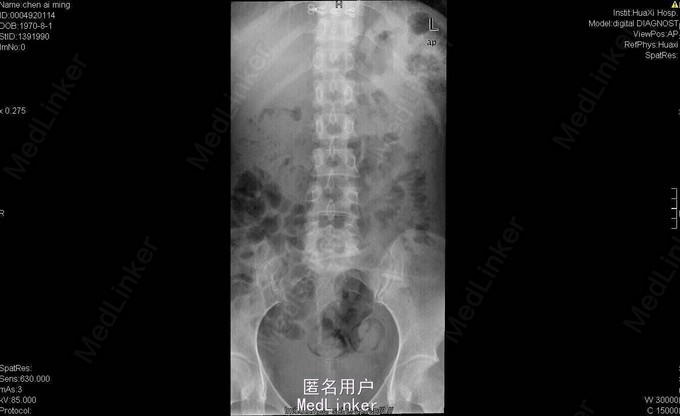

女,40岁2月,因“腰部反复疼痛2+年,加重伴双下肢疼痛、麻木1+年”入院。视:脊柱外观无畸形,皮肤未见红肿、皮疹、破溃、色斑等,无明显包块。触:腰5骶1椎棘突压痛,椎旁肌压痛,无放射痛。腰骶部感觉麻木。双下肢小腿外侧及足背感觉减退,右侧明显,其余肢体感觉正常,肌张力正常。鞍区右侧感觉减退。双下肢足背动脉搏动好。皮温正常。双膝腱减弱,踝阵挛、髌阵挛(-),巴氏征(-),右下肢直腿抬高试验(30°),直腿抬高加强试验(+),左下肢直腿抬高试验(-)。“4”字征阴性。动量:腰部不能屈伸活动,侧弯可,双下肢活动度正常,四肢肌力正常。CT及MRI:腰5骶1椎间盘脱出,腰4-5椎间盘轻度膨出,硬膜囊受压;腰5骨质增生。腰5骶1椎间盘突出症伴小关节退变。双侧椎板开窗腰5骶1椎间盘髓核摘除、内固定术。